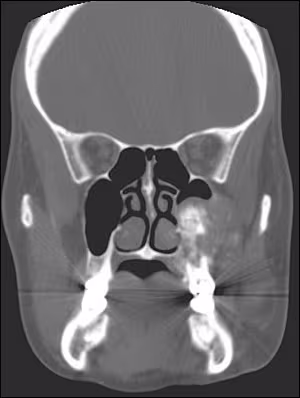

Advanced radiographic imaging using CT scans showed a mass of the left posterior maxilla extending into the maxillary sinus. Considerable expansion of the buccal and moderate expansion of the palatal cortical plate was evident. As noted in the coronal (Figure 4) as well as axial views (Figure 5), the lateral nasal wall was involved but expansion into the nasal cavity was not seen. The internal structure showed patchy calcified areas of varying density and irregular distribution.

Figure 4. CT scan, coronal section showing mass of left maxilla involving the sinus. Buccal and palatal cortical plate expansion is also seen. Irregular, patchy distribution of calcified material is seen within the lesion.